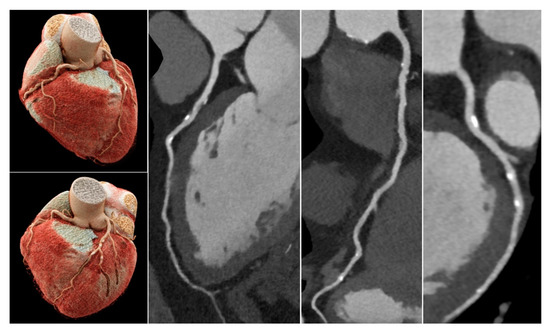

3.5. Image Quality, Assessability and CNR of the Three Main Vessels

3.7. Diagnostic Performance in the Subgroup with ICA as Reference Standard

4. Discussion